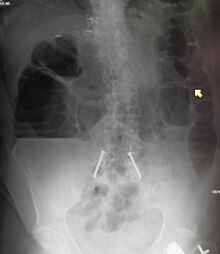

Upright abdominal X-ray of a person with a large bowel obstruction showing multiple air fluid levels and dilated loops of bowel.